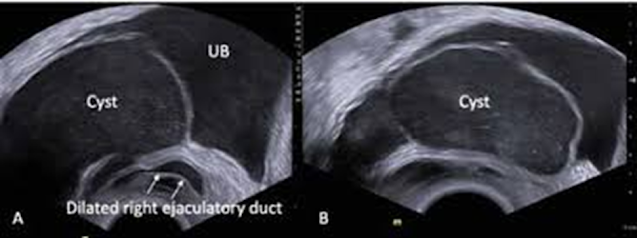

Transrectal Ultrasound (TRUS)

Transrectal sonography (TRUS) images showing dilated right ejaculatory duct communicating with dilated right seminal vesicle protruding into the urinary bladder (A); Rather than purely anechoic, there are innumerable punctate echogenic dots/ low level internal echoes seen within the cyst (B). https://doi.org/10.3126/jssn.v24i2.42837

• Useful for guiding aspiration or biopsy

• Helps assess communication with seminal vesicles